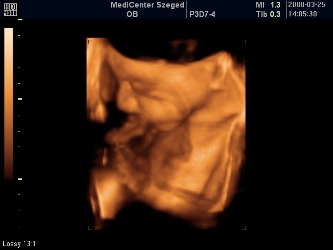

Megjöttünk a 4D-ről! :lol: 40 percet moziztunk, mert Patriknak már a legelején elege lett az egészből, befúrta a fejét a méhlepénybe, rángatta a zsinórt, rúgta a vizsgálófejet, úgyhogy nagyon nem tetszett neki. Azért lett pár kép, de nagyon megsajnáltam a kis drágámat, és én szóltam, hogy mostmár hagyjuk békén. Szerencsére minden a legnagyobb rendben, szép mindene, és befordult (múlt héten még faros volt) és ez a lényeg!!! :lol:

A méretei mostmár bizti, hogy 2 héttel nagyobbak, tehát 30 betöltött hétnek megfelelő, de a vonalzóm mostmár marad, úgyis a bébi dönti el, hogy mikor jön pontosan (de eszerint június 1-én) :lol:

A súlya: 1320 gram :shock:

Rakok képeket: kettő pofis, egy zacsis. :oops: :lol: